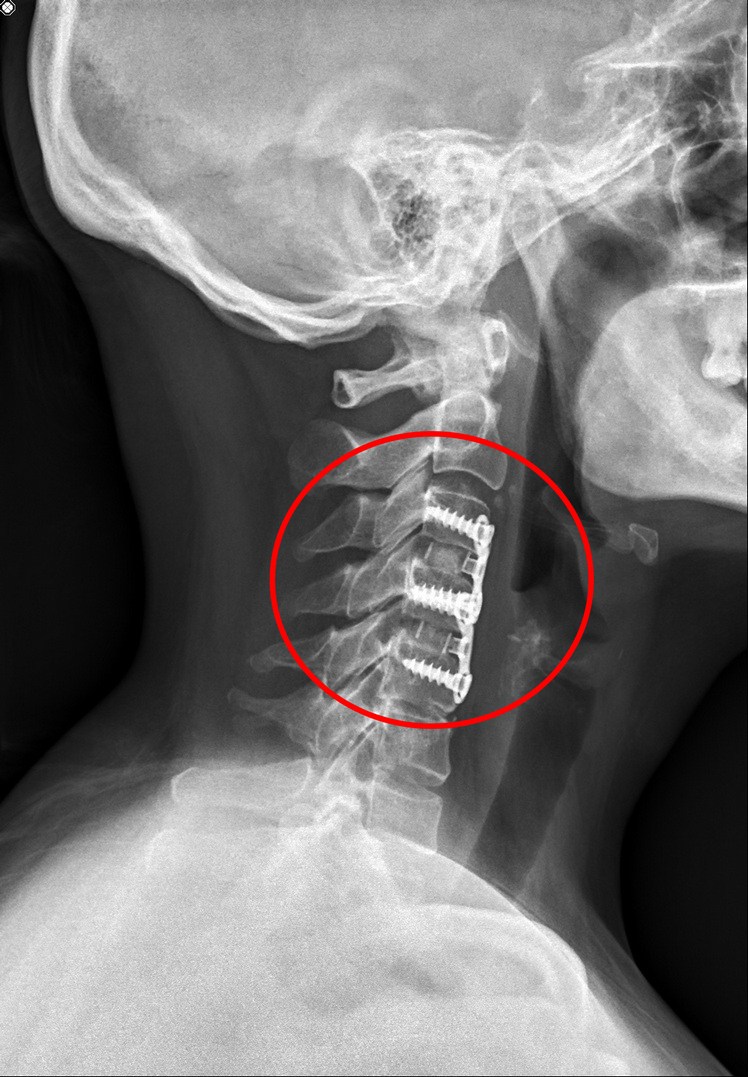

楊小姐術經過頸椎間盤切除及融合手術後,終於能平躺。

頸椎間盤切除及融合微創手術,不只傷口小、出血少,對神經及肌肉的傷害風險也最小,手術時間及住院時間短,通常病人在手術結束當天,就可以戴着頸圈行動自如。傳統手術則是傷口大、恢復期長、肌肉功能因受到破壞,術後還有可能發生肌肉疼痛與纖維化等不適。

其中手術較困難的地方是楊小姐的頸部較短,且脂肪較多,微創手術必須從楊小姐的頸部前方,經過層層的脂肪,才能進入到頸椎部位,經過兩小時,移除兩塊破裂的椎間盤手術才順利完成。手術結束當天,楊小姐就可以下床走路,行動自如,看不出是剛做完手術的病人。